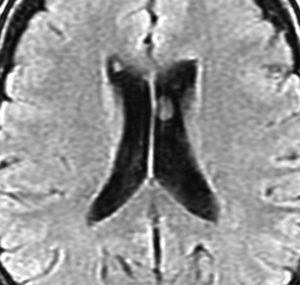

10年観察してもあまり変わらない,数が増えることがある

2012年に偶然発見され,その後,10年の経過観察されました。

2022年のものです,透明中核から出たものは少し大きくなっています。他にも数個の小さな腫瘍が脳室上壁にあるのですが,なにもしないでほっておきます。